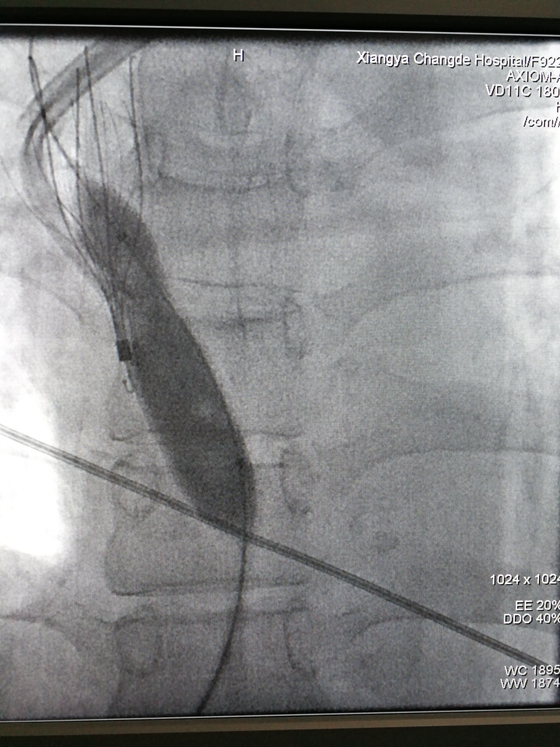

放置滤器后球囊扩张前

住院后给患者行CTV显示:右侧锁骨下静脉,右侧头臂静脉,上腔静脉上部充盈缺损,右侧颈内静脉启始部血栓形成。另外上腔静脉入口至右心房处有静脉狭窄。这就意味着,患者上述多处静脉有血栓,还有上腔静脉狭窄。如果贸然拔出右侧长期管,一旦血栓脱落随血而行,可能导致肺梗死或脑血栓,导致生命危险。成小苗主任、党智杰主治和介入科胡康新主任带领的团队汤金城主治医师,李毅副主任医师,黄彬副主任医师介入团队一同仔细分析了病情。认为可以采取左侧颈静脉置入长期导管,右侧上腔静脉放置静脉滤器防治血栓脱落,拔出右侧颈静脉长期管,球囊扩张狭窄的上腔静脉这种方案,这样既解决了血栓脱落问题,也建立了新的血管通路。2月18日,肾内科和介入科血管通路学组成功为患者置入左侧颈静脉长期管,上腔静脉放置滤器后拔出右侧颈静脉长期管,术后病人颜面浮肿消退。胡康新教授指出,静脉滤器的放置,有效的解决了血栓脱落的问题,是介入科和临床学科合作成功的范例,为病人的治疗提供一个新思路。